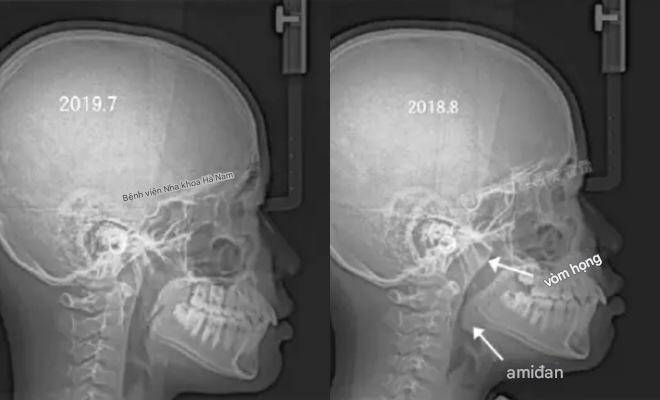

Trước đây, Giám đốc Zhang của Khoa Chỉnh nha thuộc Trường Nha khoa, Đại học Trịnh Châu, đã đăng một loạt ảnh lên Weibo:

Gia đình đưa cậu bé 11 tuổi đến khám vì miệng nhô ra bất thường.

Sau khi hỏi kỹ tiền sử, bác sĩ phát hiện cậu bé có thói quen ngủ há miệng vào ban đêm.

Kết quả chụp X-quang cho thấy đường thở mũi của cậu bị tắc nghẽn nghiêm trọng.

Đây chính là nguyên nhân khiến khuôn mặt cậu dần thay đổi.

Theo lời khuyên của bác sĩ, cậu bé đã được phẫu thuật cắt amidan và nạo VA. Một năm sau, trong lần khám theo dõi, tình trạng "miệng nhô" của cậu bé đã dần biến mất.